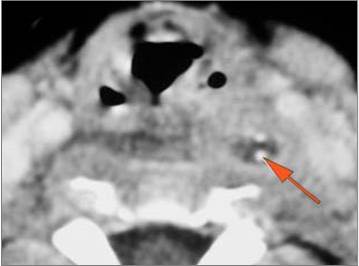

Vascular Findings

There is evidence of thrombus, thrombophlebitis or other occlusive or inflammatory process of the jugular vein or smaller venous tributaries.